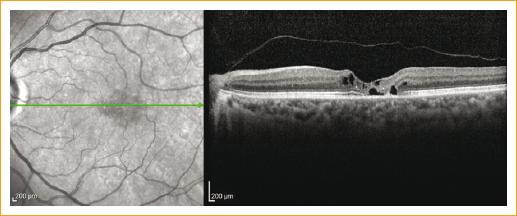

Nueve ojos (21%) presentaron neovascularización coroidea. Cuatro pacientes presentaron membrana neovascular franca, a los que se les indicó terapia con antiangiogénico intravítreo. Los cinco ojos restantes (55%) presentaron neovascularización subclínica, ya que no se observaron datos de neovascularización por clínica, OCT ni FAR, solo se detectó en la capa avascular de la OCT-A (en estos pacientes se descartaron artefactos). Los pacientes con neovascularización subclínica no presentaban mayor afección visual (LogMAR 0.3) (Figs. 1 y 2).

Figura 1 Imágenes de angiografía por tomografía de coherencia óptica de cinco pacientes con neovascularización evidenciada en el plexo avascular. La primera columna son imágenes de corte central macular, la segunda del plexo vascular superficial, la tercera del plexo profundo y la cuarta de la capa avascular.

Figura 2 Imagen superior: angiografía por tomografía de coherencia óptica (OCT-A) del ojo derecho, plexo superficial con disminución de la densidad vascular leve, en el plexo profundo se observan vasos telangiectásicos perifoveales. Imagen inferior: OCT-A del ojo izquierdo, en el plexo superficial y profundo vasos telangiectásicos, pérdida de densidad vascular y en la capa avascular neovascularización.